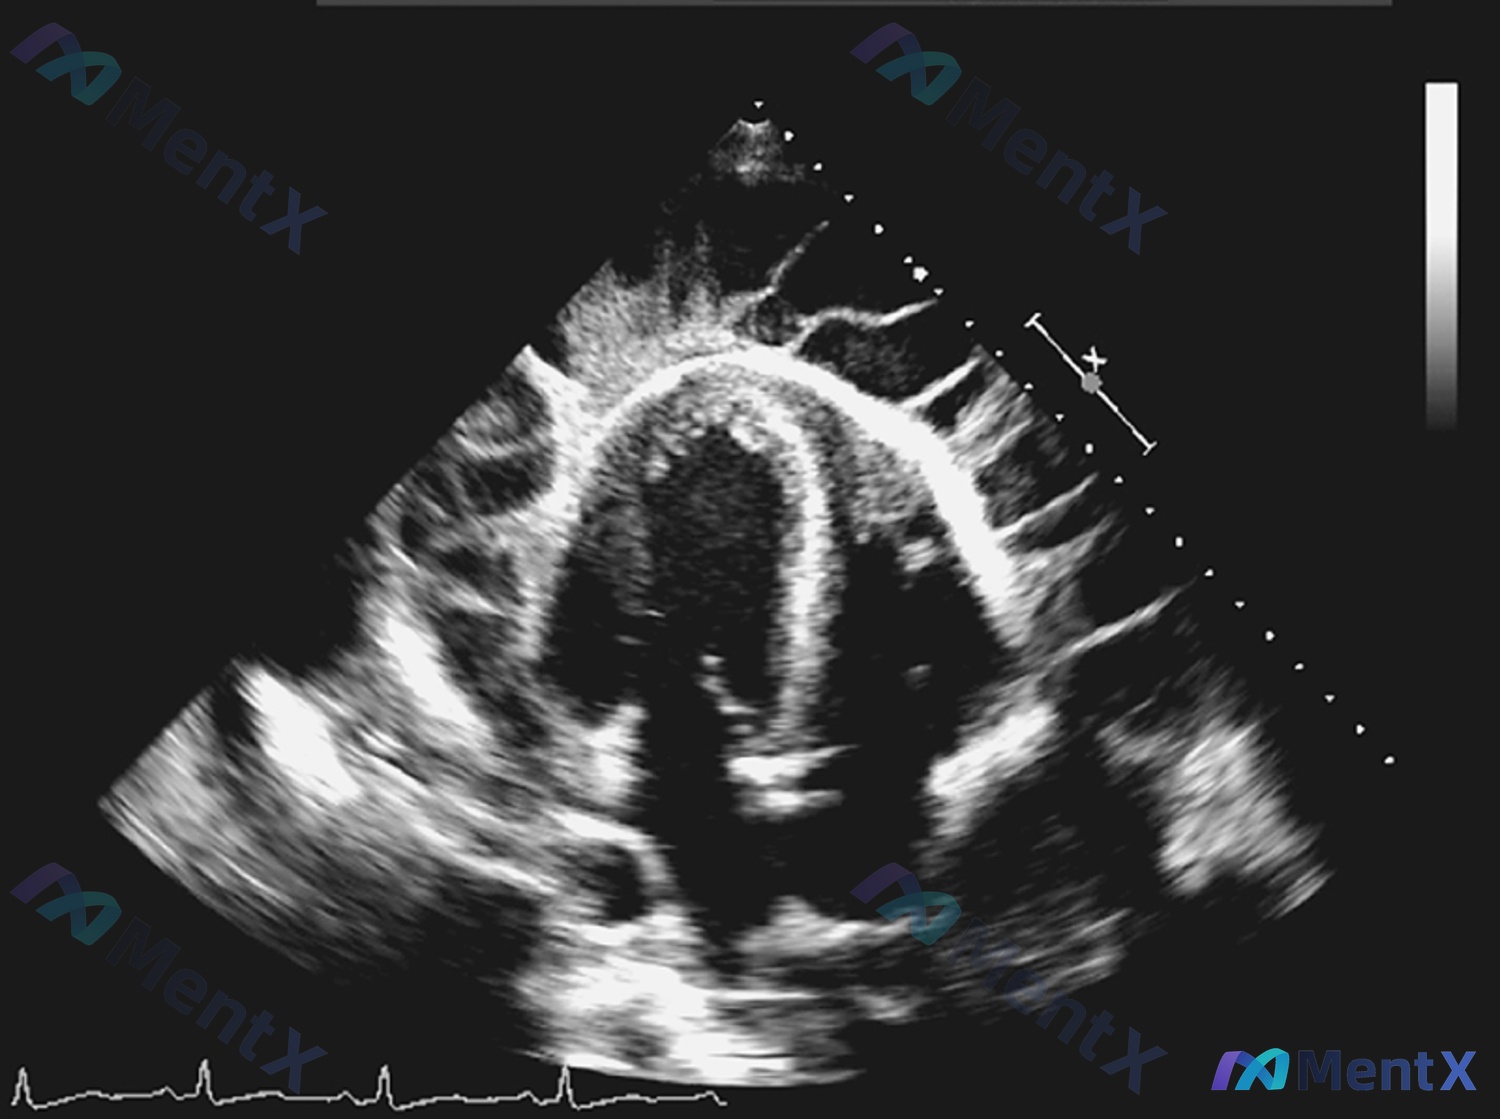

整理了一个36岁男性的心脏超声资料,先放影像分析的核心信息,大家第一眼会怎么考虑? 影像核心发现 - 切面:心尖四腔心切面 - 结构:四心腔轮廓可见,室间隔/左室侧壁厚度正常,左右心室比例大致正常,瓣膜结构未见明显赘生物/严重增厚 - 心包:未见明显液性暗区(心包积液) - 特殊:图像存在一定伪影,...